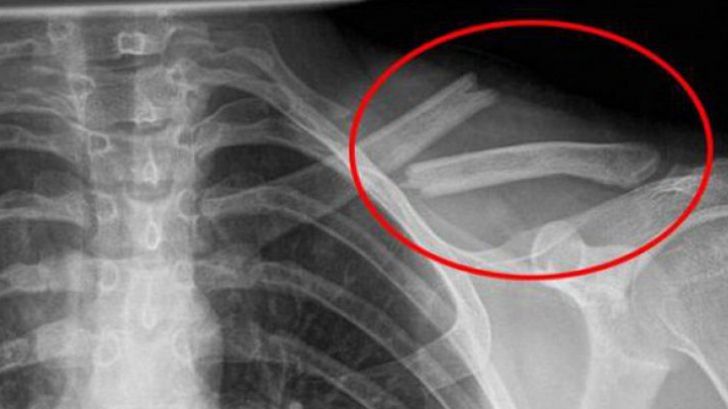

Consumul de băuturi acidulate duce la distrugerea oaselor pe termen lung, scrie girly.ro.